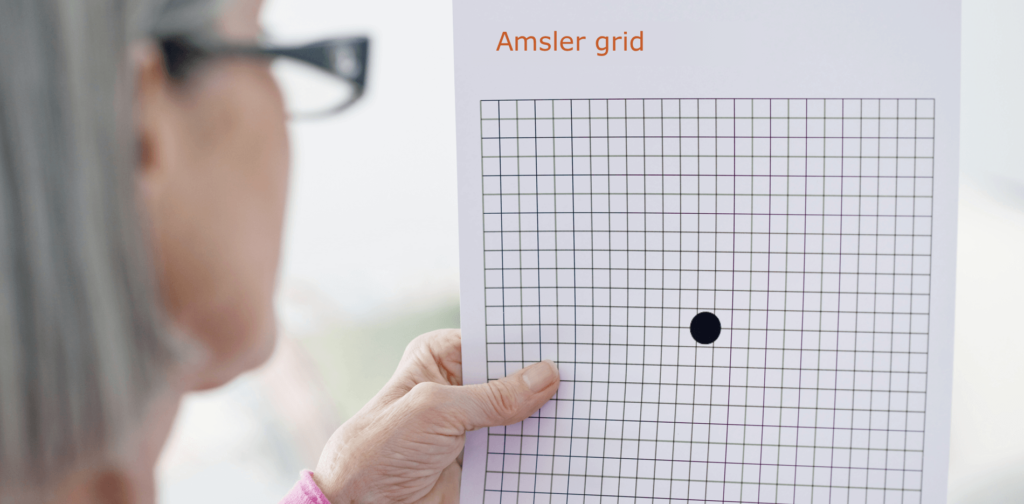

Der Amsler-Gitter-Test ist ein wichtiges1 und einfach anzuwendendes Instrument zur Selbstkontrolle, mit dem Sie Veränderungen Ihres Sehvermögens frühzeitig erkennen können. Solche Veränderungen können z. B. in Form von Verzerrungen (gerade Linien erscheinen wellenförmig) sowie verschwommenen oder dunklen Flecken auftreten.

Der Amsler-Gitter-Test eignet sich jedoch nicht als Grundlage für die Diagnose und ist kein Ersatz für regelmäßige Augenuntersuchungen. Die AMD kann ausschließlich durch eine Augenuntersuchung, einschließlich einer Untersuchung der Makula, durch einen Augenarzt diagnostiziert werden. Wird eine Veränderung des Sehvermögens anhand des Amsler-Gitter-Tests festgestellt, kann dies auch ein Anzeichen für eine andere Augenkrankheit als die AMD sein.

Wenn Sie irgendeine Veränderung Ihres Sehvermögens feststellen, ist es wichtig, so bald wie möglich einen Augenarzt aufzusuchen.

Sie können ein Amsler-Gitter herunterladen und ausdrucken, indem Sie auf den unten stehenden Link klicken oder den Abschnitt „Hilfsmittel“ auf der Website besuchen. Der Download enthält ein Amsler-Gitter sowie eine Schritt-für-Schritt-Anleitung, wie Sie es zur Überprüfung Ihres Sehvermögens verwenden können.